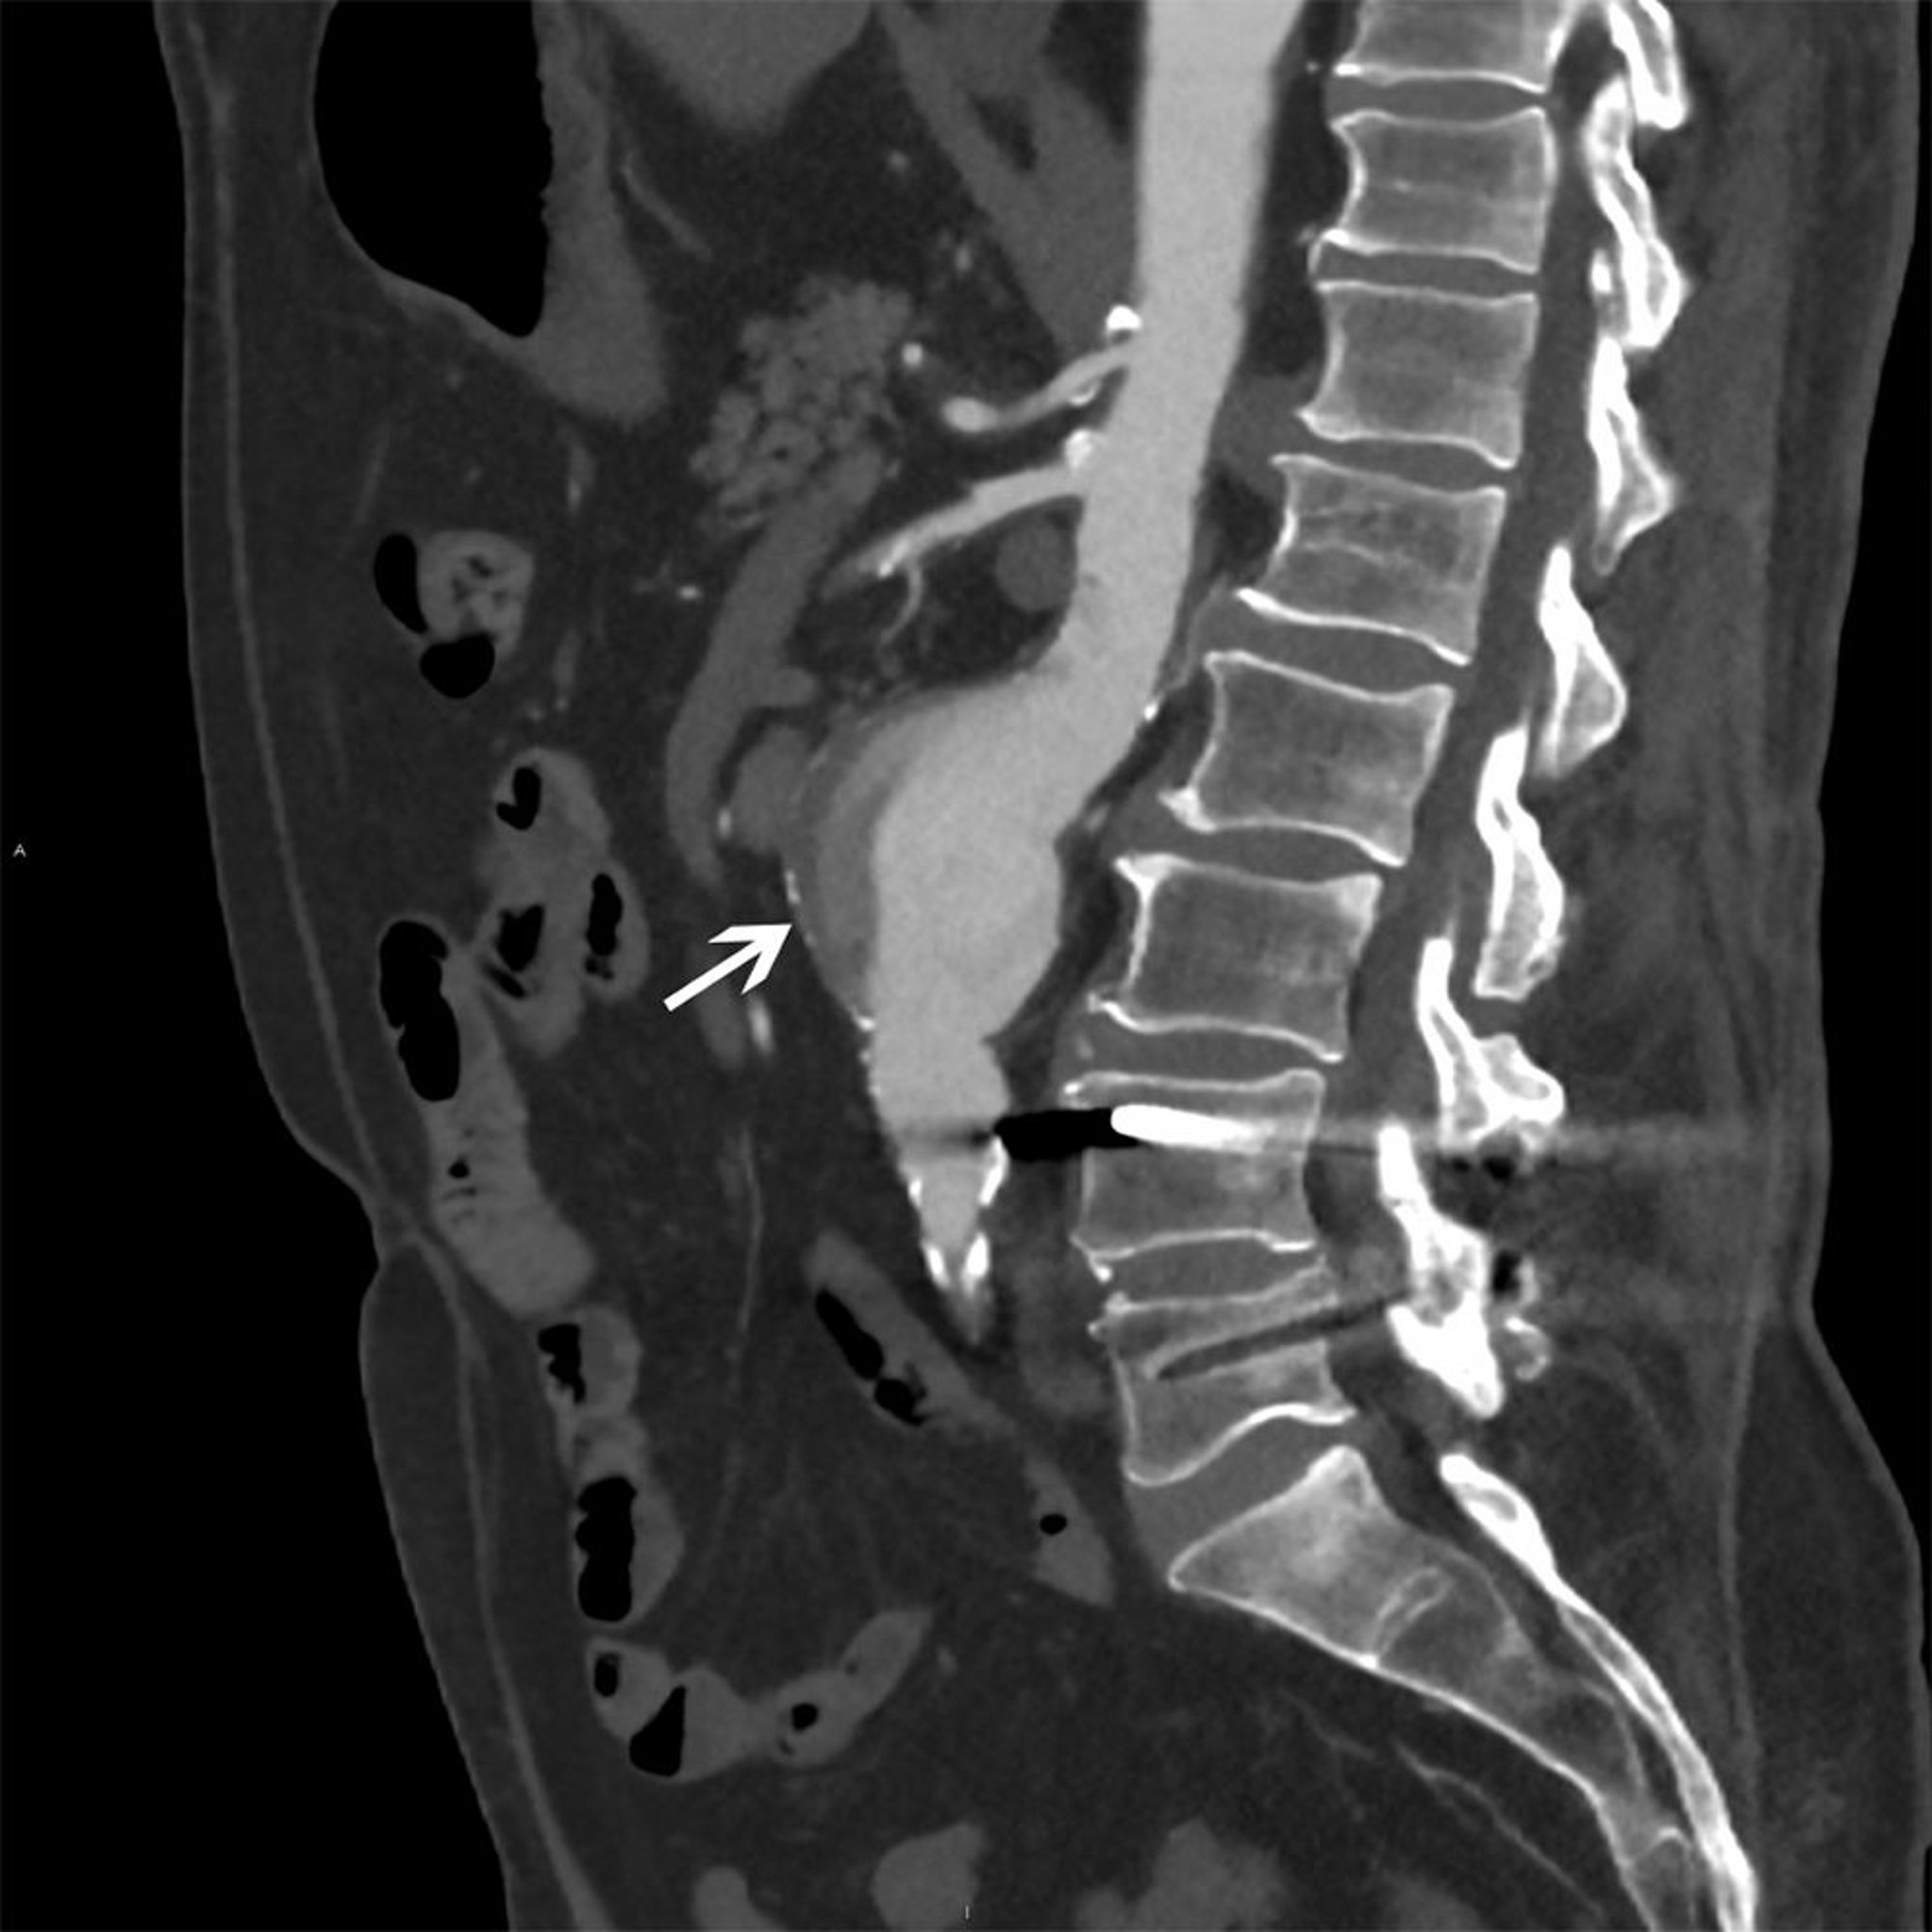

Aneurisma da aorta abdominal (TC)

A seta branca mostra um aneurisma aórtico abdominal medindo 5 cm com fluxo heterogêneo e placa mural.